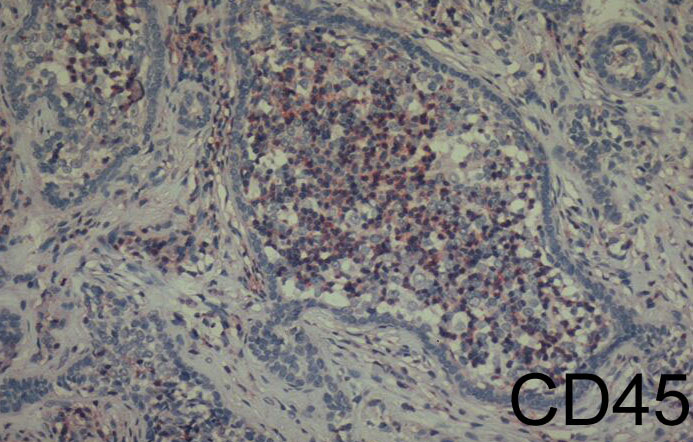

Cutaneous lymphadenoma =الغدوم اللمفاوي الجلدي